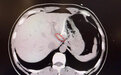

直到CT检查时,医生才惊讶地发现,李先生肝脏左叶靠近胃贲门处有一条细长的高密度影,形似鱼刺。原来,那根鱼刺在吞咽后穿透了胃壁,从贲门区域钻入肝脏,引发感染与脓肿。在简单进行肝脓肿介入穿刺引流后,当地外科医生评估后认为,要彻底清除异物,需要进行左半肝切除手术,但这对于李先生来说,创伤大、风险高,他难以接受。

患者李先生影像检查。本文图片均来自复旦大学附属中山医院